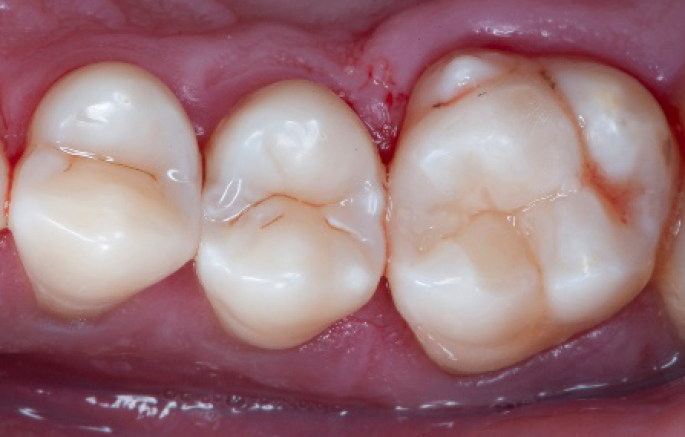

Before

Initial situation: an old class I composite restoration on 1.6. New caries on the mesial wall. Presence of plaque and inflammation.

Diagnosis

• On the x-ray examination, a mesial translucency (initial caries) was found on tooth 1.6.

• The tooth presented an old class I composite restoration.

• Marginal inflammation and plaque were present.

• No symptoms were referred by the patient.